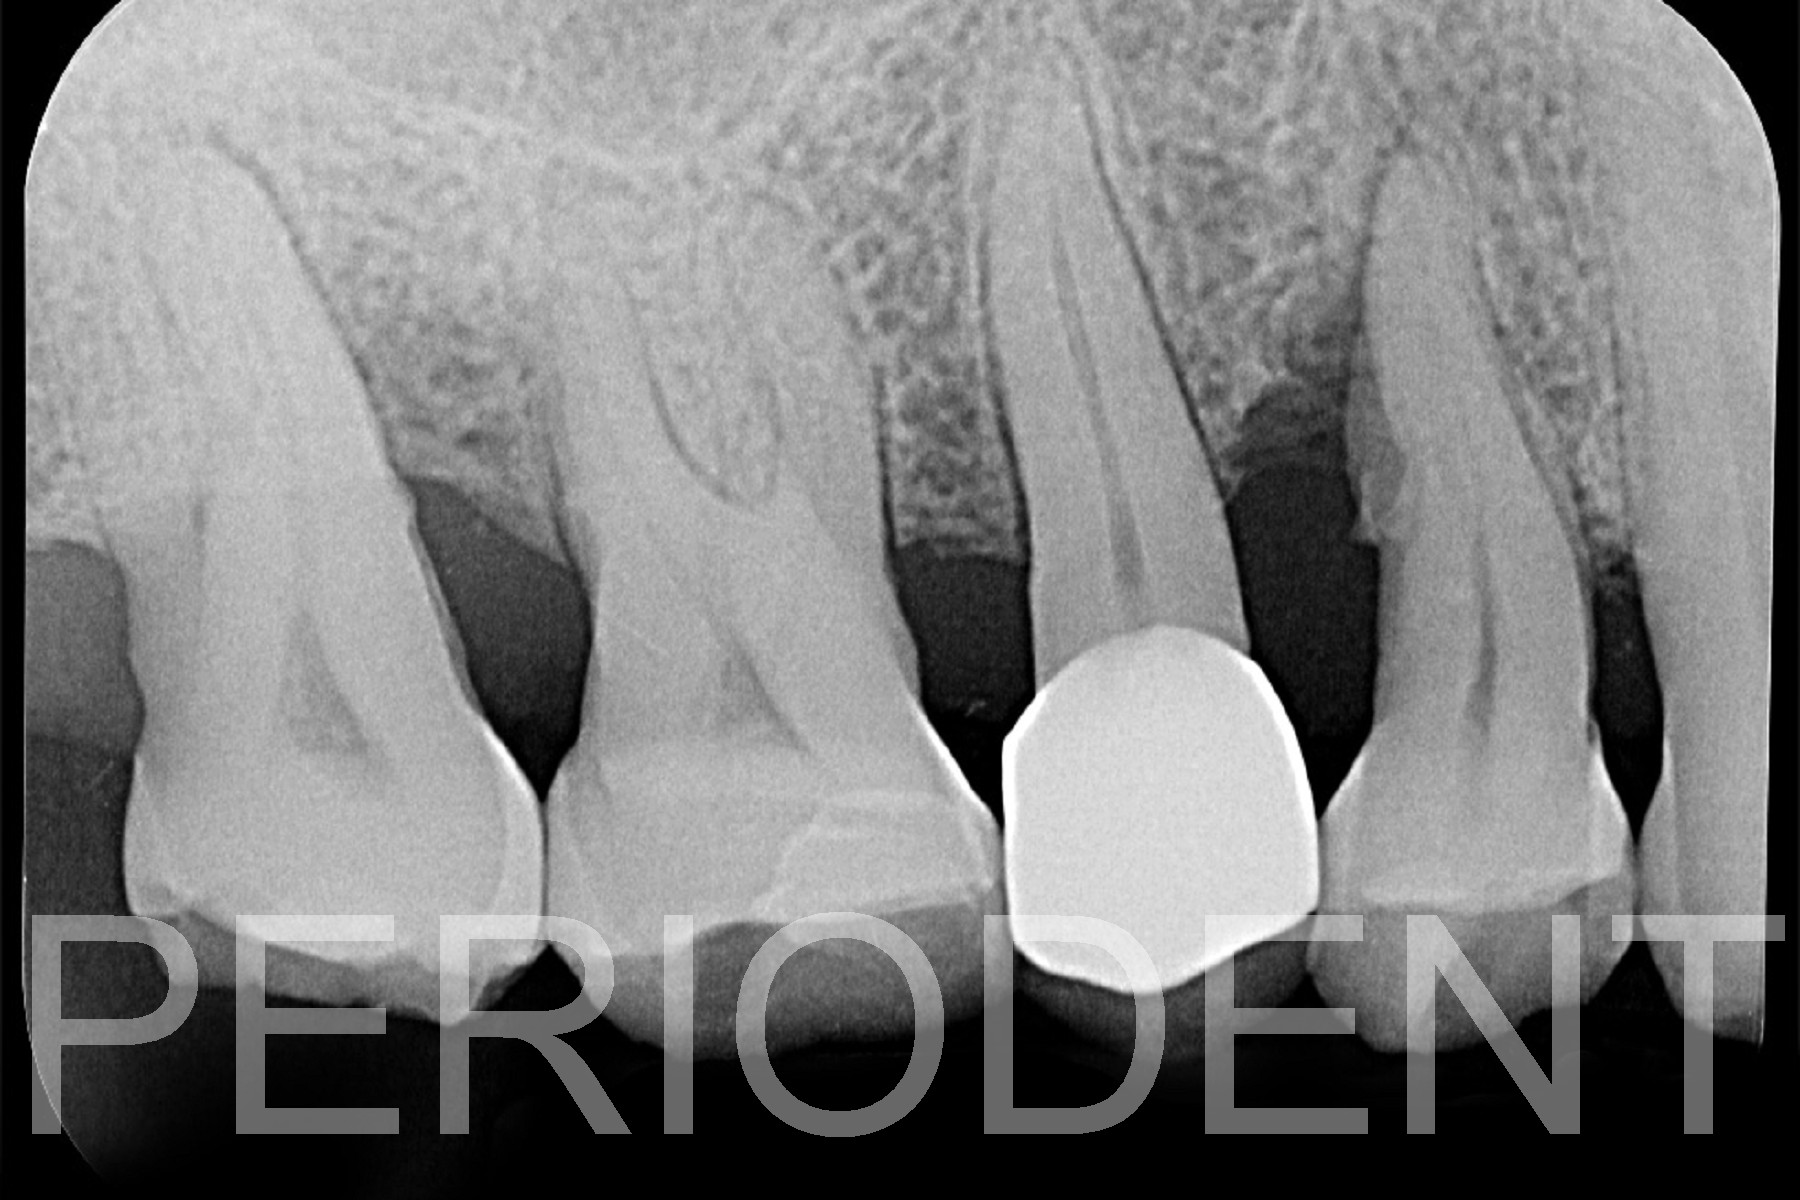

1. 患者為63歲男性,右上區經過牙周基本治療後

8個月,右上第一,二小臼齒仍有6厘米囊袋

2. 手術時,利用顯微刀片作M-MIST切開,並用

ER-YAG雷射清除Granulation Tissue,作Root

Planing及縫合